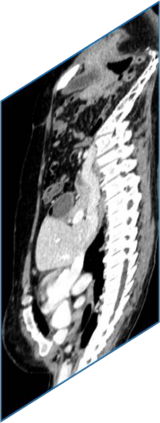

Due to the constraints of the imaging device and high cost in operation time, computer tomography (CT) scans are usually acquired with low intra-slice resolution. Improving the intra-slice resolution is beneficial to the disease diagnosis for both human experts and computer-aided systems. To this end, this paper builds a novel medical slice synthesis to increase the between-slice resolution. Considering that the ground-truth intermediate medical slices are always absent in clinical practice, we introduce the incremental cross-view mutual distillation strategy to accomplish this task in the self-supervised learning manner. Specifically, we model this problem from three different views: slice-wise interpolation from axial view and pixel-wise interpolation from coronal and sagittal views. Under this circumstance, the models learned from different views can distill valuable knowledge to guide the learning processes of each other. We can repeat this process to make the models synthesize intermediate slice data with increasing inter-slice resolution. To demonstrate the effectiveness of the proposed approach, we conduct comprehensive experiments on a large-scale CT dataset. Quantitative and qualitative comparison results show that our method outperforms state-of-the-art algorithms by clear margins.